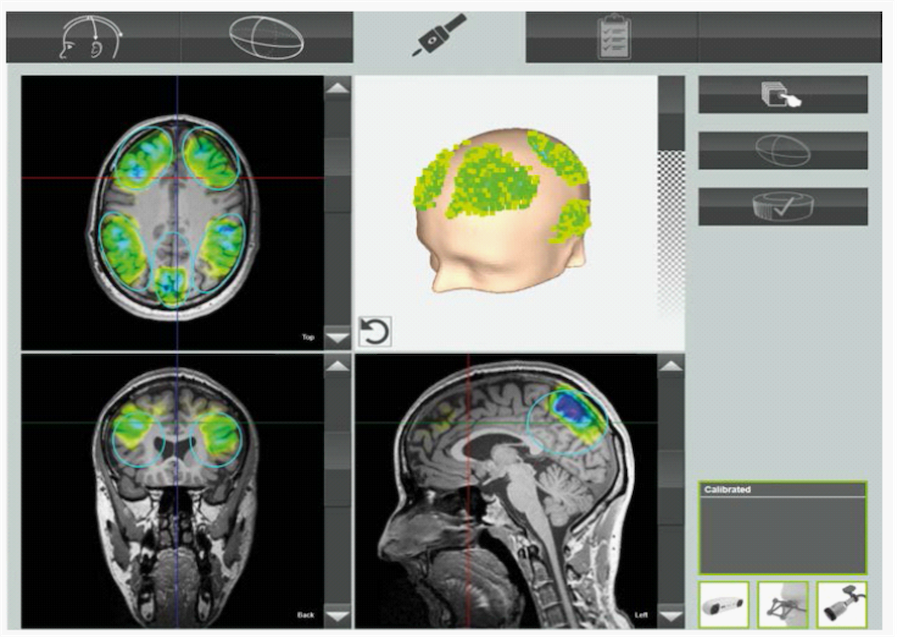

TPS predstavlja savremenu, neinvazivnu neuromodulacionu tehnologiju koja fokusirane akustične pulseve visoke energije usmerava u ciljane strukture mozga uz pomoć precizne neuronavigacije.

Na ovaj način se u ciljnim strukturama mozga podstiču neuroplastičnost, prokrvljenost i metabolička aktivnost nervnog tkiva, uz mogućnost prostorne preciznosti do jednog kubnog milimetra (približno debljina vrha grafitne olovke).

TPS koristi kratke (3 μs), fokusirane ultrazvučne pulseve visokih frekvencija (200–500 kHz) koji prolaze kroz lobanju i ciljano deluju na moždano tkivo, izazivajući blage mehaničke vibracije na ćelijskom nivou.

Tretman se sprovodi u specijalizovanim neurološkim ordinacijama pomoću TPS uređaja Neurolith, uz asistenciju napredne neuronavigacije koja omogućava precizno ciljano delovanje sa preciznošću do 3 mm. Pacijent sedi u udobnom položaju dok lekar aplicira impulse na određene tačke mozga prema individualno određenom planu stimulacije. Postupak je u potpunosti bezbolan i ne zahteva posebnu pripremu.